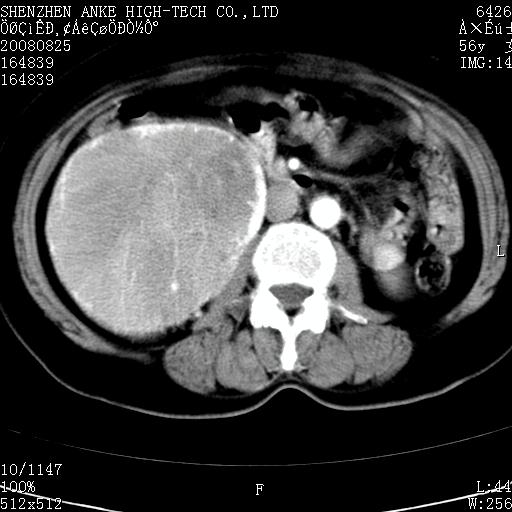

患者,女性,56岁,腰痛3年,查:右腹部约8x10cm肿块,固定,无压痛;8月23日在外院做了平扫,发现右肾巨大肿块(外院具体诊断不祥);今天在我院做了静脉肾盂造影,示:右肾明显增大,分泌功能明显减弱。

1)考虑右肾癌并右肾静脉瘤栓形成。2)脂肪肝。